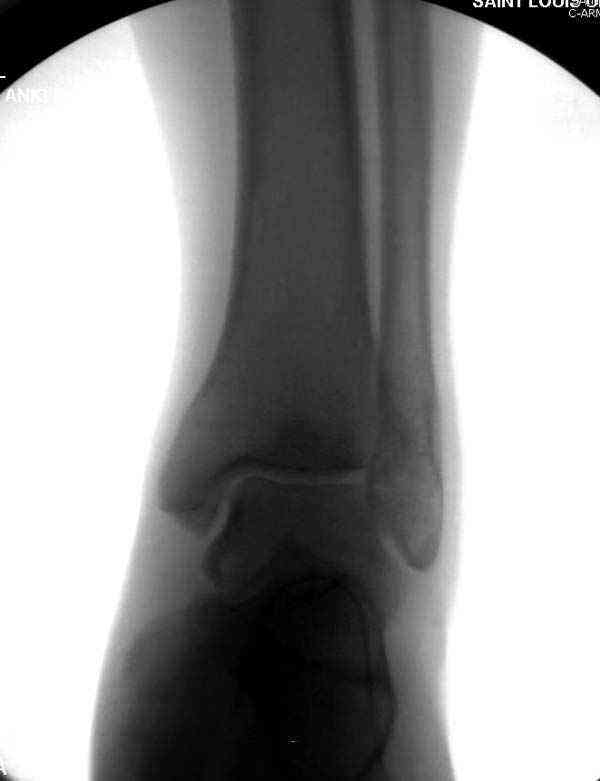

Нет первичных снимков, перелом очень низкий и под большим сомнением диагноз разрыва синдесмоза. Медиальная сторона отрепонирована на "хорошо" и, по-видимому, прорезание проволоки произошло во время операции. Без снимков трудно судить о высоте малоберцовой, а лодыжка находится в варусе. Лагирование получилось, но возле тонких шурупов передне-задний шуруп выглядит немного тяжеловато.

Коллеги правы, что при рутинных переломах достаточным бывает обычные снимки с мортизом. А стрессовые рентгенограммы могут уточнить, есть ли разрыв синдесмоза.

Здесь несколько частных случаев: перелом голеностопа со сравнительными снимками и разрыв синдесмоза, а также медиальная Hook пластина.